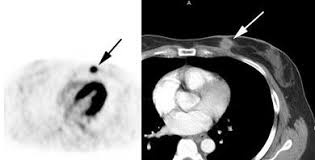

Fdg Pet Pet Ct And Breast Cancer Imaging Radiographics from pubs.rsna.org A breast pet scan is often very specific and sensitive and is approved for patients. It's an effective imaging test for finding cancer and learning its stage. Bone scans, positron emission tomography (pet), and computed tomography (ct) all continue to be employed alone or in combination for the detection of breast cancers suspected to have spread. Breast positron emission tomography (pet) scan is an imaging test that uses a tracer (radioactive substance) to look for symptoms of breast cancer. Pet scan is a type of test that may be used in cancer treatment. Pet scans can be used to determine how much cancer is in a person's body and how far the cancer has spread, which is called staging. It can be done along with a ct scan. Pet scans can be useful for evaluating people after breast cancer has already been diagnosed, in a number of different ways:

The test has only a limited ability to detect small tumors. Pet scan for breast cancer a positron emission tomography (pet) scan is an imaging test that uses a radioactive substance (called a tracer) to look for potential spread of breast cancer. In some instances, cancers may not show on the scan. Combining a pet scan with an mri or ct scan can help make the images easier to interpret. Pet scans can be used to determine how much cancer is in a person's body and how far the cancer has spread, which is called staging. This tracer can help identify areas of cancer that an mri or ct scan may miss. With cancer cells, they appear as bright spots due to its higher metabolic rate compared to normal cells. However, the pet scan uncovers every unusual activity in the body and is more sensitive than any other existing imaging test. Pet/ct scan can accurately localize lymph node metastasis and help to monitor the response to chemotherapy. Breast positron emission tomography (pet) scan is an imaging test that uses a tracer (radioactive substance) to look for symptoms of breast cancer. Pet scans can also help to assess whether metastatic breast cancer is responding to the treatment. Pet scans are not used to screen women for breast cancer. Pet/ct scans using axumin tracer, approved by fda last year and newly approved by medicare in some areas, are starting to be done at different locations.

Thus, pet/ct detected a primary breast mass and metastatic lymphadenopathy that mammography and ultrasonography failed to detect a finding not previously reported, to our knowledge. Mammograms take advantage of the fact that most of the female breast is fat tissue, so it's relatively transparent to the low doses of radiation used in mammography. One example is a combined pet and ct scan (known as pet/ct), available in some centers. Does anyone know if a ct scan can show breast cancer or colon cancer rather than the standard mammogram or colonoscopy? When breast cancer cancer spreads.